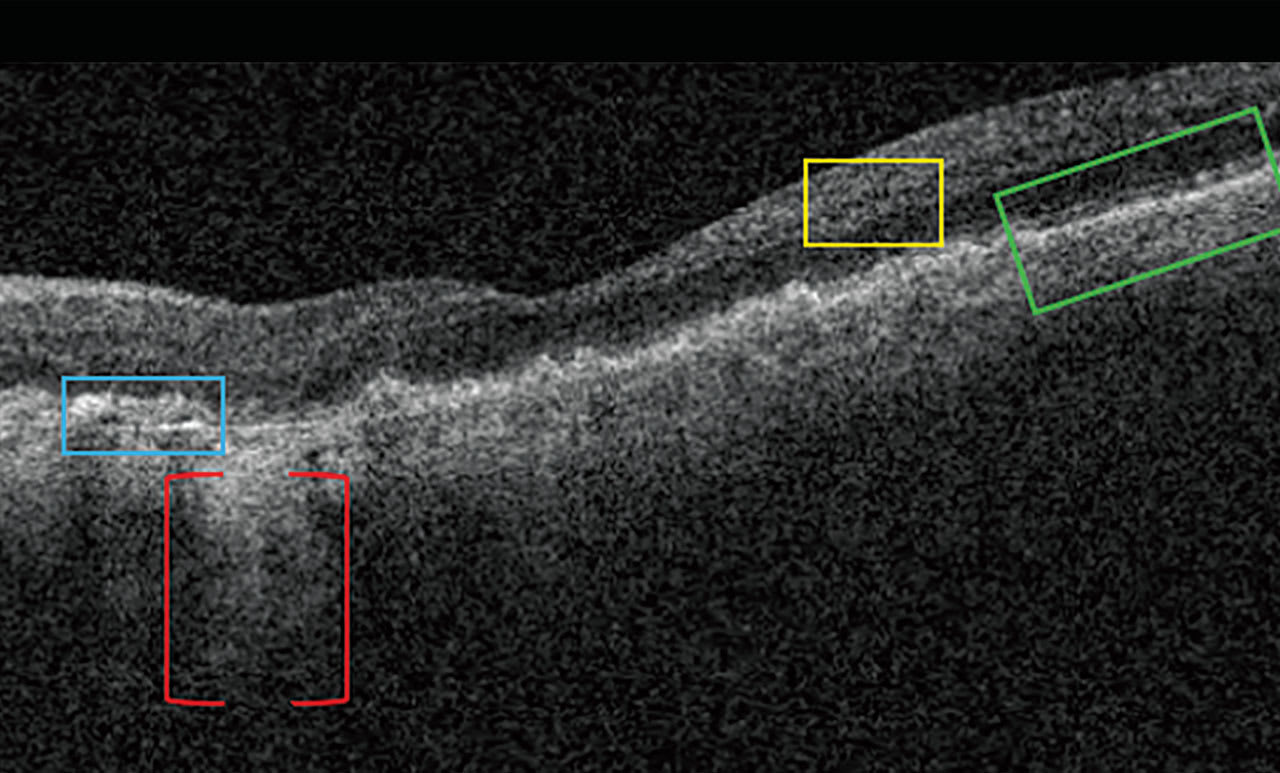

Nascent GA is drusen-associated incomplete RPE and outer retinal atrophy (iRORA) without CNV.1,2 On OCT, it appears as a subsidence of the outer plexiform layer (OPL) and the inner nuclear layer (INL), along with a wedge-shaped band within the OPL.1 The lesion’s boundaries are defined by “an abrupt increase in choroidal reflectivity below Bruch’s membrane; the RPE, photoreceptor, and choriocapillaris layer loss; and external limiting membrane absence/descent”.1 Also, nascent GA and iRORA increase progression risk to GA. In fact, eyes that have some of the findings of iRORA are at high risk of developing advanced AMD3 (Figure 2).